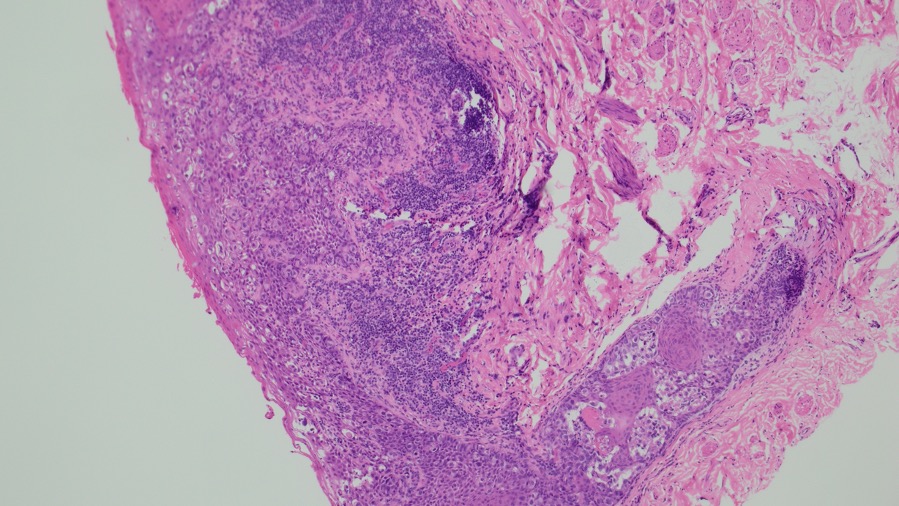

Large round malignant cells with pale cytoplasm and enlarged nucleolus and prominent nucleoli are present within the epidermis. The cytoplasm contains mucin. Differential diagnosis include HSIL, Paget disease (primary or secondary), and melanoma in situ. The lesional cells are strongly positive for CK7, CK20, CAM5.2 and GATA3, scattered positive for p63; and patchy staining for p16, negative for ER and SOX10. High-risk HPV-ISH is negative.

Patient's history of invasive high-grade urothelial carcinoma is shown. The tumor cells showed similar morphological features to the tumor cells in current specimen. The findings are compatible with secondary involvement by previously diagnosed urothelial carcinoma.

Due to morphological similarity both architecturally and cytologically, precise diagnosis based on H&E alone can be challenging, and IHC can be overlap. The current case highlight the importance of clinical history in establishing an accurate diagnosis for patients with an extension of urothelial carcinoma into the GYN tract.